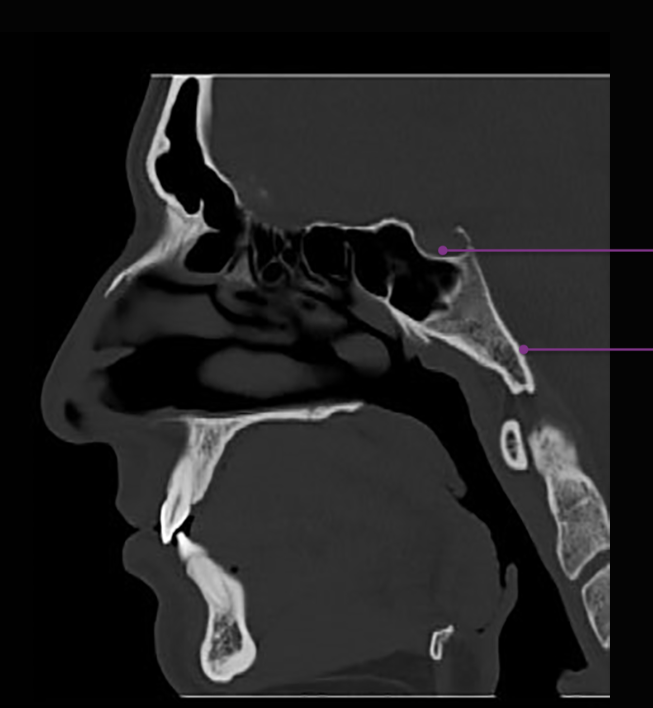

Agger Nasi cell - Agger means “mound” or “heap” in Latin. This structure is the anterior-most ethmoid air cell. It is located inferolateral to the frontal recess, the channel which communicates between the anterior ethmoid and frontal sinuses. The agger nasi cell is an important landmark for front sinus surgery because the roof of the cell is the floor of the frontal sinus.